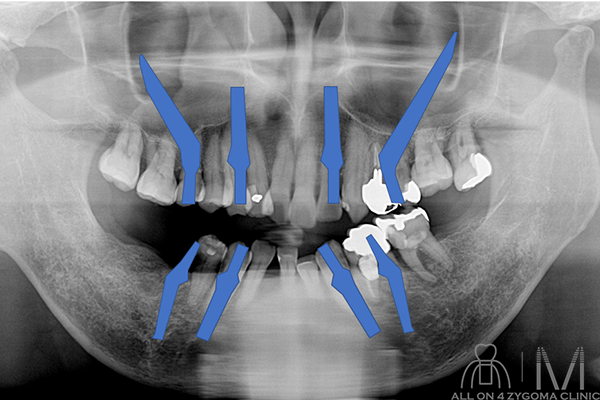

治療計画

手術所見

術式:静脈内鎮静法下、上下顎All-on-4

(多数歯抜歯術、ザイゴマインプラント埋入術)施行